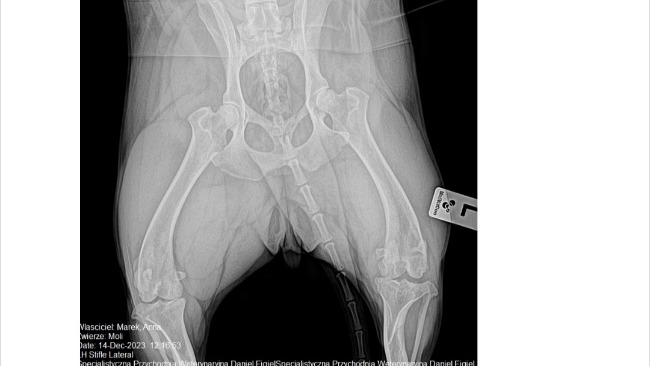

Stwierdzono u niej kulawiznę, bolesność kolana, zmiany zwyrodnieniowe stawu kolanowego, zmiany zwyrodnieniowe lewego łokcia- dysplazję. Konieczna jest operacja. Niestety koszt zabiegu to ponad 4000 zł, co przekracza moje możliwości finansowe. 😭😭😭